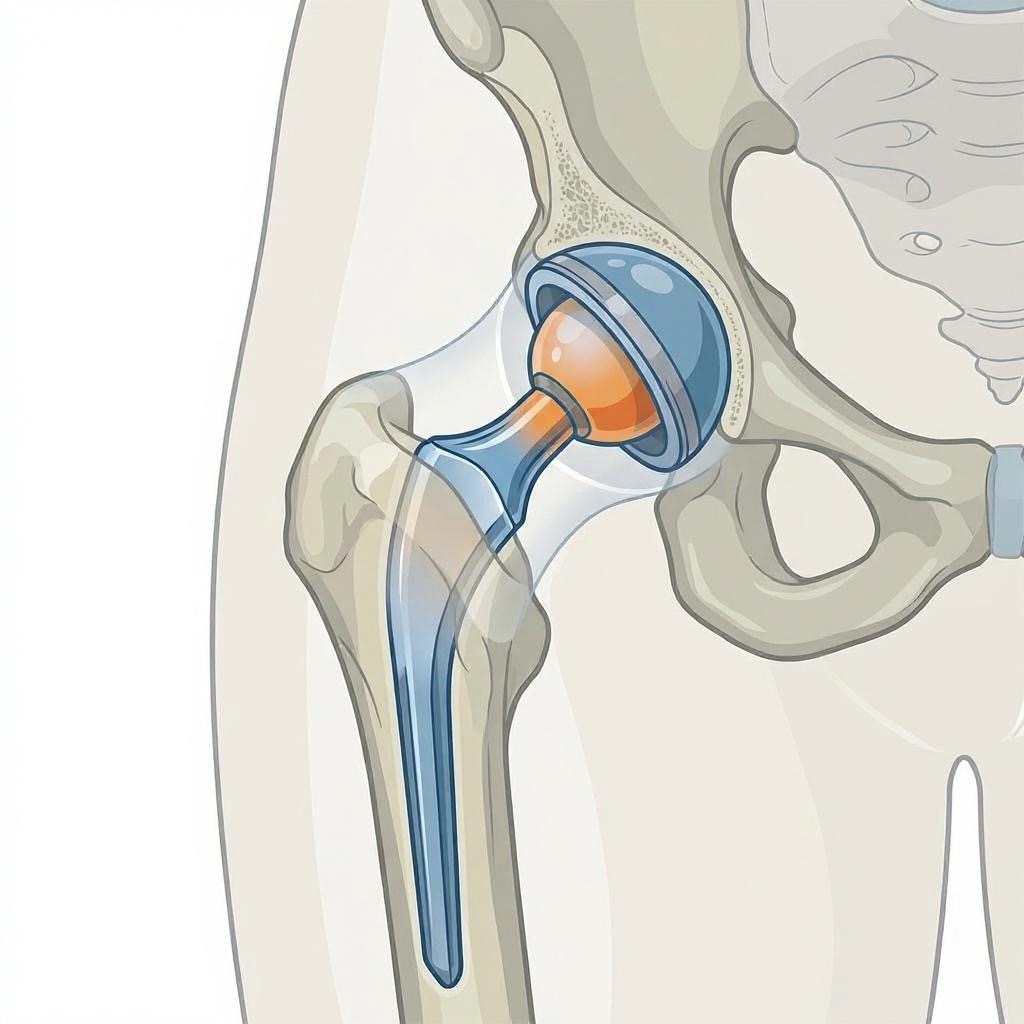

Was ist der Unterschied zwischen Teil- und Vollprothese?

- Teilprothese (Schlittenprothese/unikondyläre Prothese): Ersetzt nur den geschädigten Teil des Kniegelenks (medial oder lateral). Geeignet bei isoliertem Kompartmentschaden mit intakten Bändern.

- Vollprothese (Totalendoprothese): Ersetzt alle drei Gelenkkompartimente. Notwendig bei fortgeschrittener Arthrose in mehreren Bereichen.